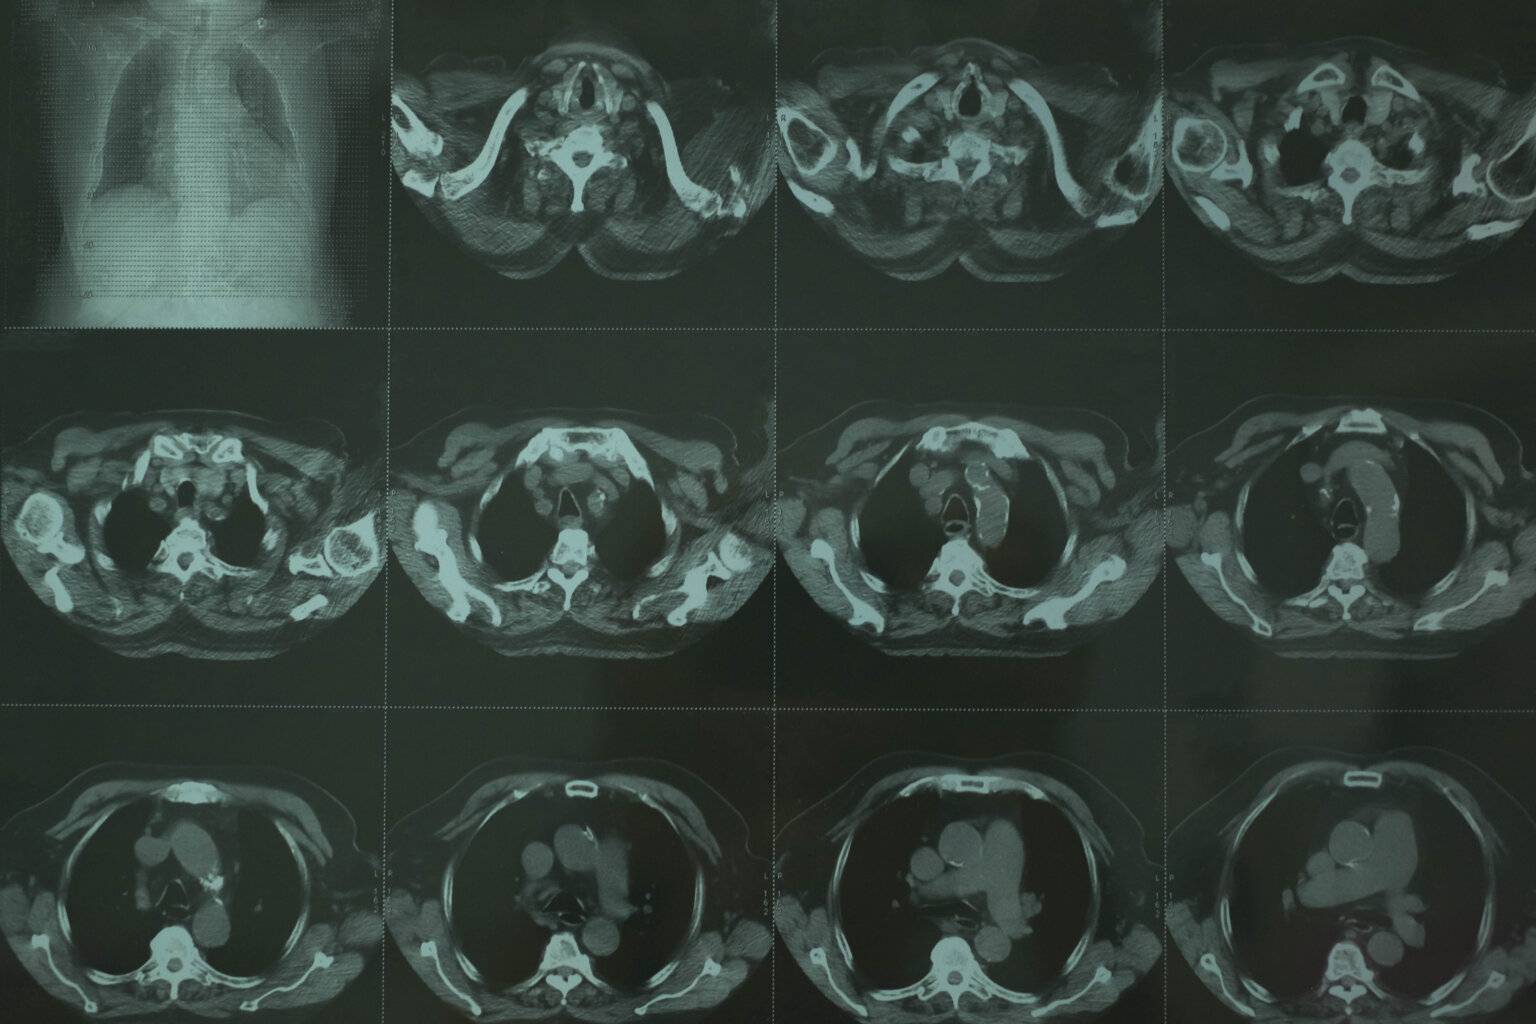

- Scannen: Der CT-Scanner verwendet Röntgenstrahlen, um mehrere Bilder des Abdomens aus verschiedenen Winkeln aufzunehmen. Der Scanner dreht sich um den Patienten und nimmt dabei detaillierte Querschnittsbilder des Bauchraums auf.

CT Abdomen Befundung – CT Abdomen welche Organe sieht man?